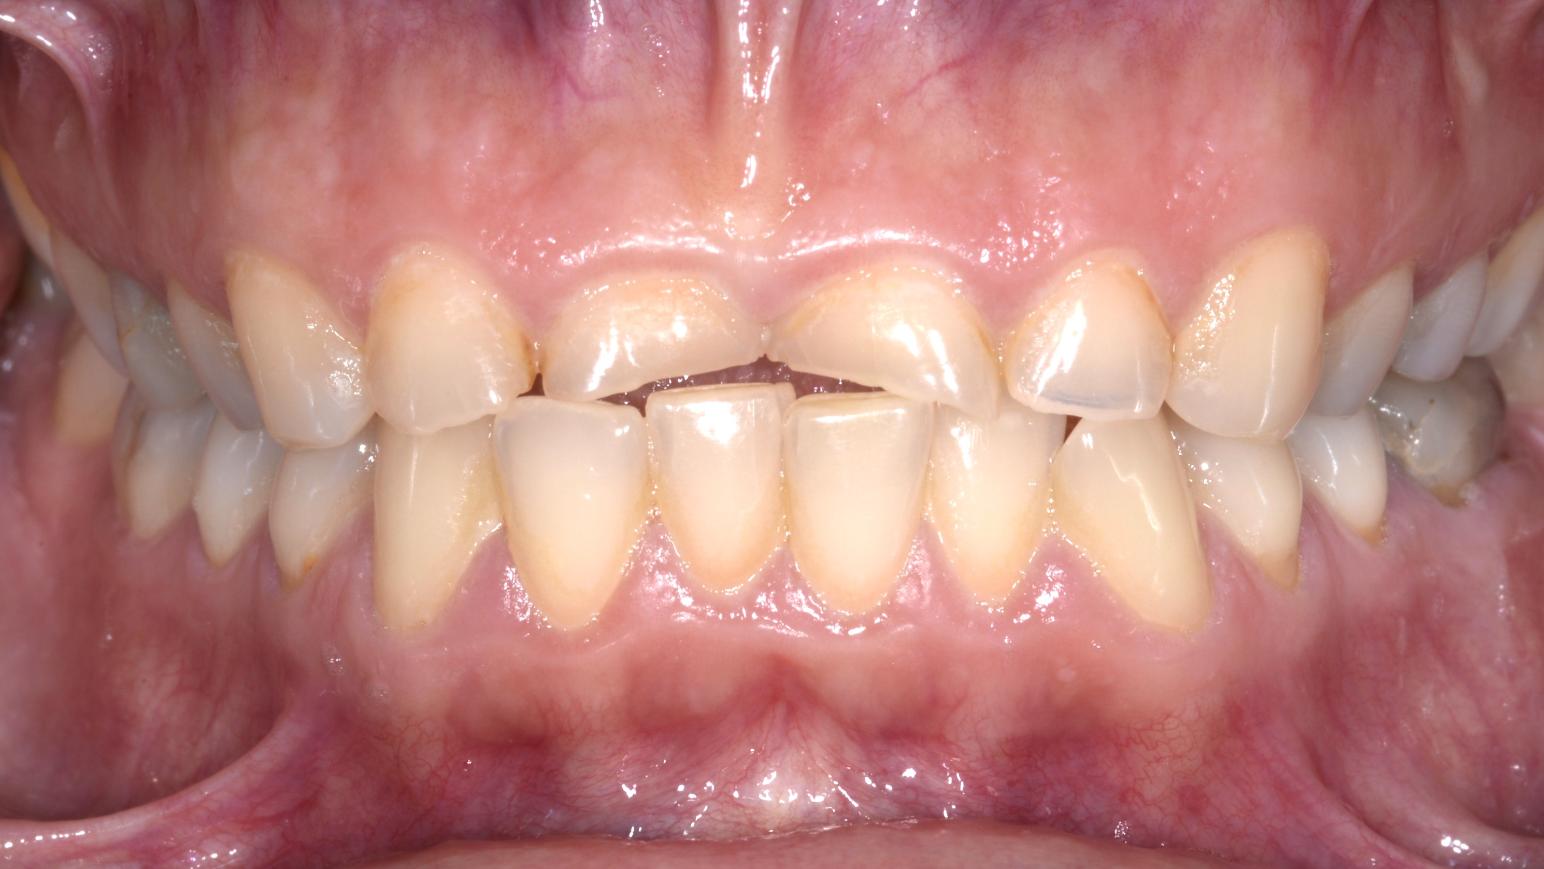

I danni del bruxismo prima del trattamento

Dopo il trattamento